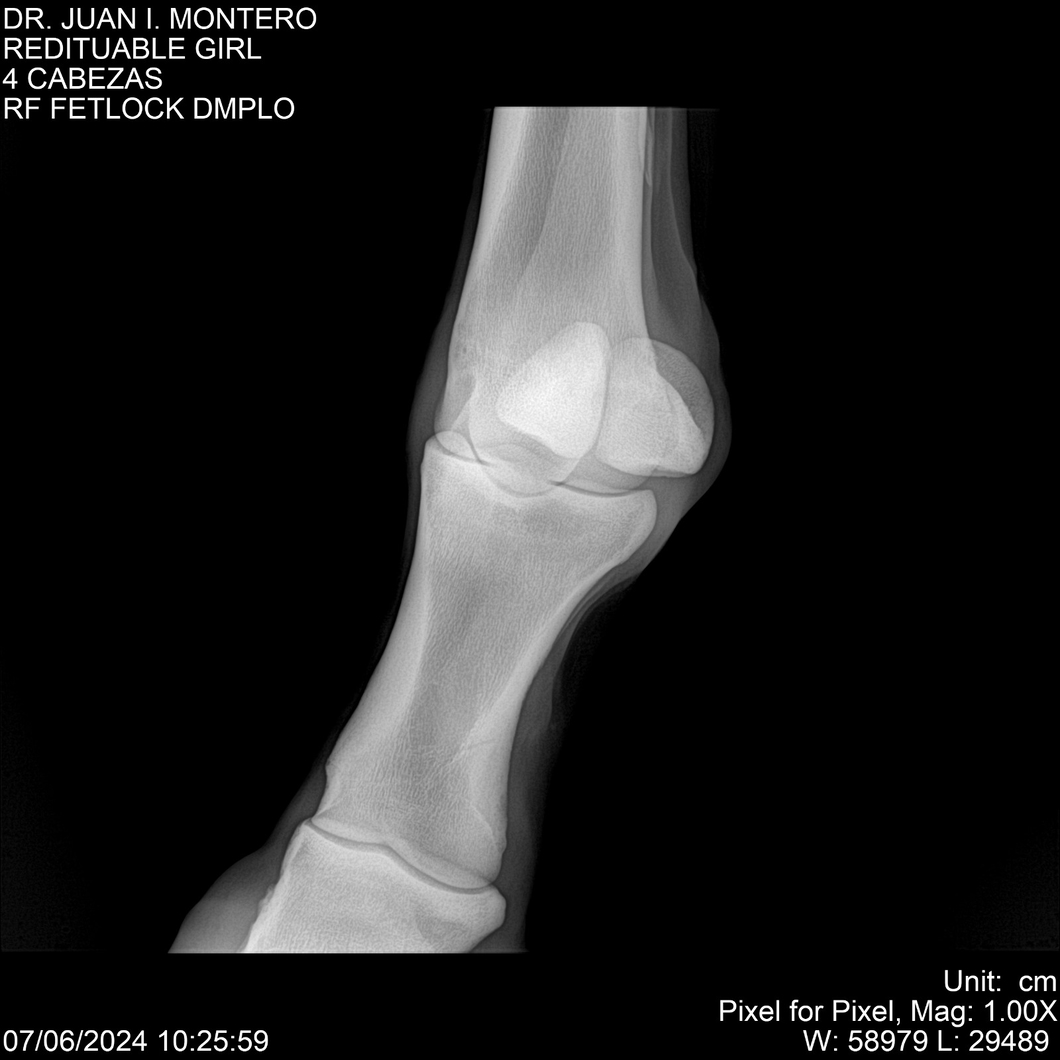

LOTE 19, REDITUABLE GIRL Lote Anterior Volver al remate Lote Siguiente Ficha Contacto Montevideo - Ficha del Lote Identificador: #281096 Categoría: Yeguarizos Montevideo - 79 Visualizaciones ClicData Contacto Empresa: Abelenda N. R., Walter Hugo Nombre*: Teléfono* : E-mail* : Mensaje Enviar Registrese gratis Este contenido Exclusivo está disponible sólo para usuarios registrados Ingresar